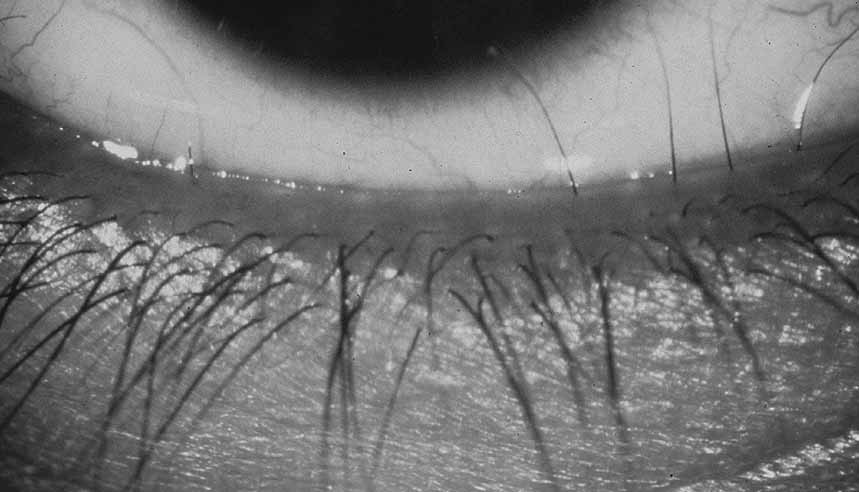

Distichiasis refers to the presence of a second row of eyelashes that arise from the meibomian glands (Fig. 12). (This is in distinction to trichiasis in which eyelashes arise from their normal location but are misdirected). Distichiasis can be inherited either alone (OMIM 12630) or, more commonly, as part of the lymphedema-distichiasis (LD) syndrome (OMIM 153400).184,224 The aberrant lashes in distichiasis may cause ocular irritation and photophobia.

Fig. 12 Distichiasis. Several lashes are arising from meibomian gland orifices and are rubbing against the globe.

The LD syndrome is an autosomal-dominant disorder characterized by congenital distichiasis and peripheral lymphedema that usually begins at approximately the age of puberty. Other reported associated features include lower eyelid ectropion, congenital ptosis, photophobia, cleft palate, webbing of the neck, vertebral anomalies, extradural cysts, varicose veins, renal abnormalities, and congenital heart disease.225–230 Fang et al. recently described mutations in the forkhead transcription factor, FOXC2, in families with LD.231 Numerous additional mutation—all predicted to cause haploinsufficiency of FOXC2—have been reported in LD families.185,232–235 Brooks et al. recently reported a family presenting with distichiasis and no lymphedema who had a truncating mutation in FOXC2.236 This pedigree suggests that LD syndrome and simple distichiasis may be points along a phenotypic continuum, rather than separate genetic defects. Ophthalmologists should also be aware that LD syndrome might present as distichiasis alone and should counsel their patients accordingly.

Ocular irritation and photophobia may be treated conservatively with lubrication. Severe cases may cause corneal scarring and may be treated with cryotherapy, lid-splitting procedures, and/or tarsal excision.237–241